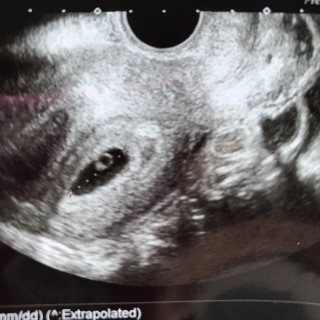

12週目での4Dエコー! この日からお腹のエコーに切り替わりました。 こんなにはっきり赤ちゃんが見えるなんて、本当に感激です。「頭かいてるね~!とても元気ですよ」と先生。想像以上に手足が動いていました! 寝ているときはあまり動かないそうで、起きてる時をみれてよかったです(*´-`)

半年前に流産をして、この12週の検診まで毎日ハラハラでした。「手が顔の横にあってこれ可愛いんじゃない」と言って40枚くらいの写真の中から先生が選んでくれました。次は16週です!

5本の指!左のお手てがくっきり。初めて経腹エコーしたけど、ボヤけてて写りが悪く…今まで通り下からエコーでちゃんと写りました!次回は、経腹エコーできるかな?楽しみ!!ベビーちゃんの頭は2.4cm。アベレージは13wの大きさでした!